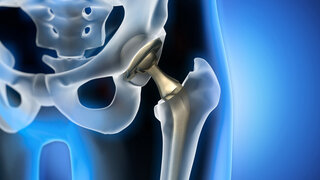

Bakteriämien bei Patienten mit künstlichen GelenkenZahnärztliche Vorsorge wichtiger als Antibiotikaprophylaxe? Anlässlich einer neuen Studie zur Antibiotikaprophylaxe vor Zahn-OPs bei Endoprothesenträgern macht die Deutsche Gesellschaft für Endoprothetik auf die Bedeutung der zahnärztlichen Prophylaxe aufmerksam. 28.01.2022 ZahnmedizinProthetik